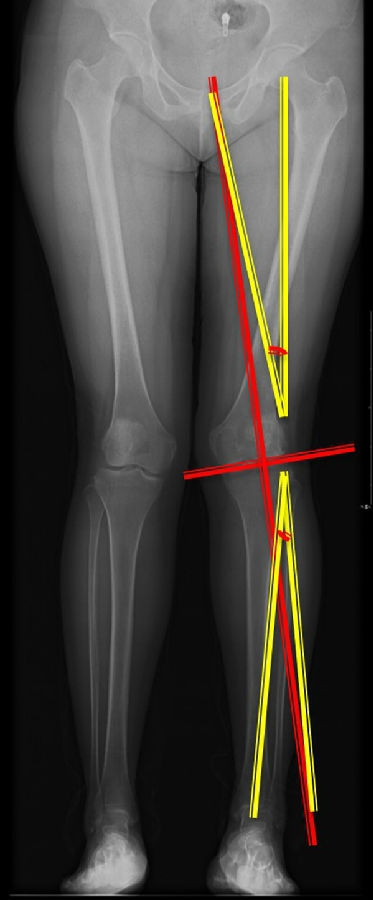

以股骨侧合页为旋转中心,以股骨头中心到合页的距离为半径,进行旋转,直到该线段与目标力线相重合,此时重合角度即为股骨需要闭合的角度,同时胫骨侧也能计算出开放的角度。此患者需要股骨闭合14°,胫骨开放8°。

患者二,女性,膝外翻,膝外侧疼痛。通过做畸形分析后发现,该患者同时存在股骨侧畸形、胫骨侧畸形和关节内畸形(LDFA=82°,MPTA=104°,JLCA=6°)。

对于这类病人如何进行术前设计的关键点就在于目标力线应如何设计。要在骨性截骨的时候纠正骨性畸形,关节内畸形要通过关节内的方法解决。因为JLCA不平行,所以要同时画股骨侧关节线和胫骨侧关节线,并垂直于股骨侧关节线做出股骨侧目标力线,垂直于胫骨侧关节线做出胫骨侧目标力线。

根据各自目标力线,分别计算股骨内侧闭合和胫骨内侧闭合角度。

此患者股骨内侧闭合6°,经股内侧闭合13°。